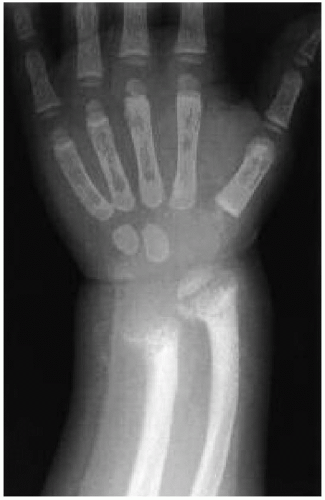

Vitamin D Metabolism Radiology : Vitamin D Resistant Rickets Is An X Linked Dominant Bone ... : Child with rickets has metaphyseal fraying and cupping of the distal radius and ulna.